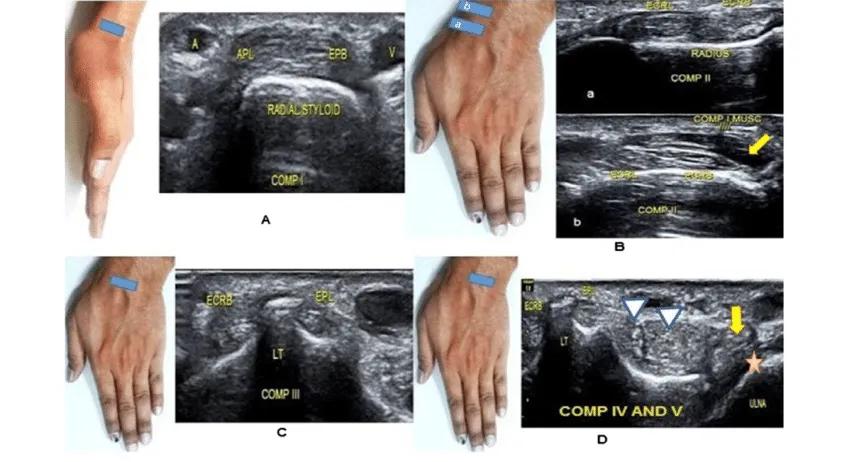

对于腱鞘炎的诊断其实并不困难,如果患者出现了上面所描述的一些症状,比如屈伸手指的疼痛,比如在手指指根的部位能够触及较硬的增粗肌腱,比如出现了屈伸手指的困难,需要掰一下才能完成活动,这种情况我们称之为扳机指,就要怀疑存在肌腱的腱鞘炎症,那么此时我们进行肌骨超声检查就可以很好的帮助我们进行诊断了,并没有必要一定要进行核磁检查或者是X线检查才能明确诊断,这一点大家一定要切记。